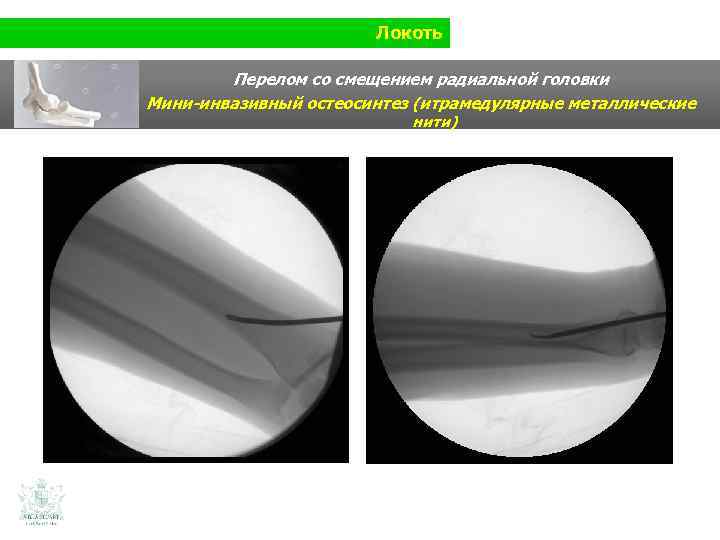

Локоть Перелом со смещением радиальной головки

Локоть Перелом со смещением радиальной головки Мини-инвазивный остеосинтез (итрамедулярные металлические нити)